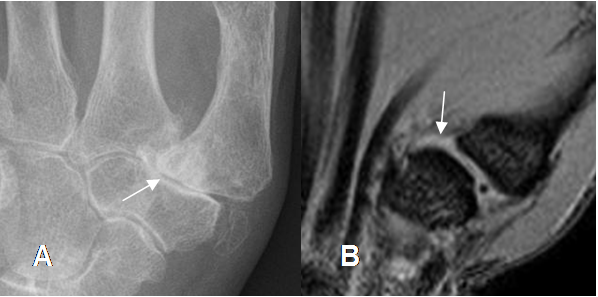

Fig 100. Artropatía degenerativa.

A: Rx AP. Cambios degenerativos en la articulación carpometacarpiana del pulgar, con esclerosis y disminución del espacio.

B: Presencia de líquido en la articulación carpometacarpiana del pulgar, por enfermedad degenerativa.